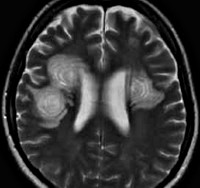

G37.5 Концентрический склероз [Бало]